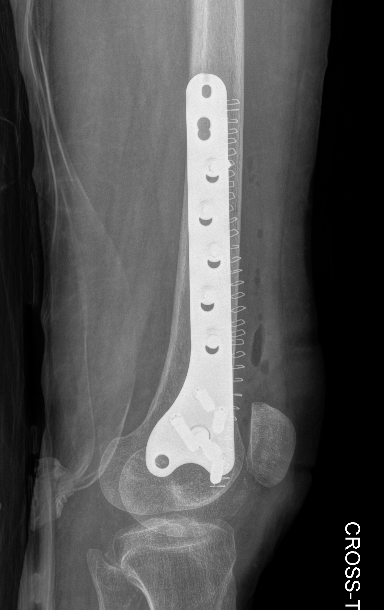

Xray

Lateral plate

Retrograde IM nail

Surgical Technique